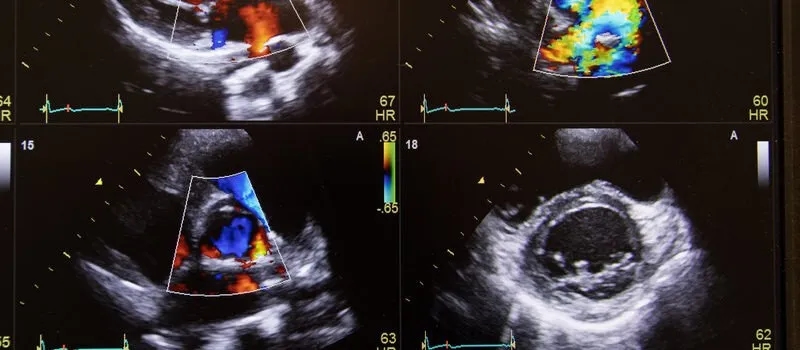

Podczas badania ultradźwięki są wysyłane przez specjalną głowicę, a ich odbicia od poruszających się krwinek są analizowane przez urządzenie. Wyniki są prezentowane na monitorze w formie kolorowych map i wykresów, co ułatwia interpretację danych. W kolejnych częściach artykułu przyjrzymy się szczegółowo, na czym polega to badanie, jakie są jego zalety oraz jak wygląda jego przebieg.

- Wyniki są prezentowane w formie barwnych map i wykresów.

Podczas badania, lekarz może zmierzyć prędkość i kierunek przepływu krwi. To ważne, ponieważ pozwala na wykrycie problemów, takich jak zwężenia naczyń, zakrzepy, czy niewydolność zastawek żylnych. Wyniki badania są prezentowane na monitorze w formie barwnych map lub wykresów, co ułatwia ich interpretację. Co istotne, badanie jest bezbolesne i zwykle nie wymaga skomplikowanego przygotowania.

Podstawą działania badania dopplerowskiego jest efekt Dopplera, który opisuje zmianę częstotliwości fal dźwiękowych w zależności od ruchu źródła dźwięku względem obserwatora. W przypadku USG Doppler, fale ultradźwiękowe są emitowane przez głowicę, a ich odbicia od krwinek czerwonych są analizowane przez specjalistyczne urządzenie. To pozwala na dokładne pomiary przepływu krwi w naczyniach.

W badaniu wykorzystuje się zaawansowane technologie, takie jak aparaty ultradźwiękowe z funkcją Dopplera. Te urządzenia są w stanie generować obrazy w czasie rzeczywistym, co jest kluczowe dla diagnostyki. Dzięki temu lekarze mogą szybko i skutecznie ocenić stan naczyń krwionośnych oraz zidentyfikować ewentualne problemy zdrowotne.